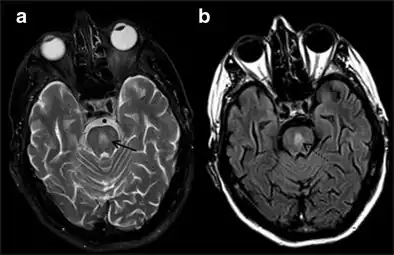

It can be diagnosed clinically in the appropriate context, but may be difficult to confirm radiologically using conventional imaging techniques. Changes are more prominent on MRI than on CT, but often take days or weeks after acute symptom onset to develop. Imaging by MRI typically demonstrates areas of hyperintensity on T2-weighted images.[27]

Central Pontine Myelinolysis -a & b) axial T2W and FLAIR images at the level of pons show central pontine hyperintensity